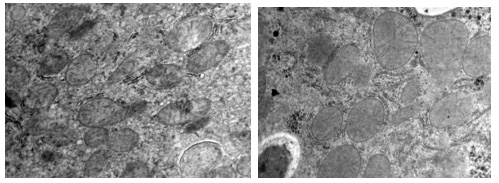

案例 不同組小鼠細(xì)胞電鏡圖(15000×)